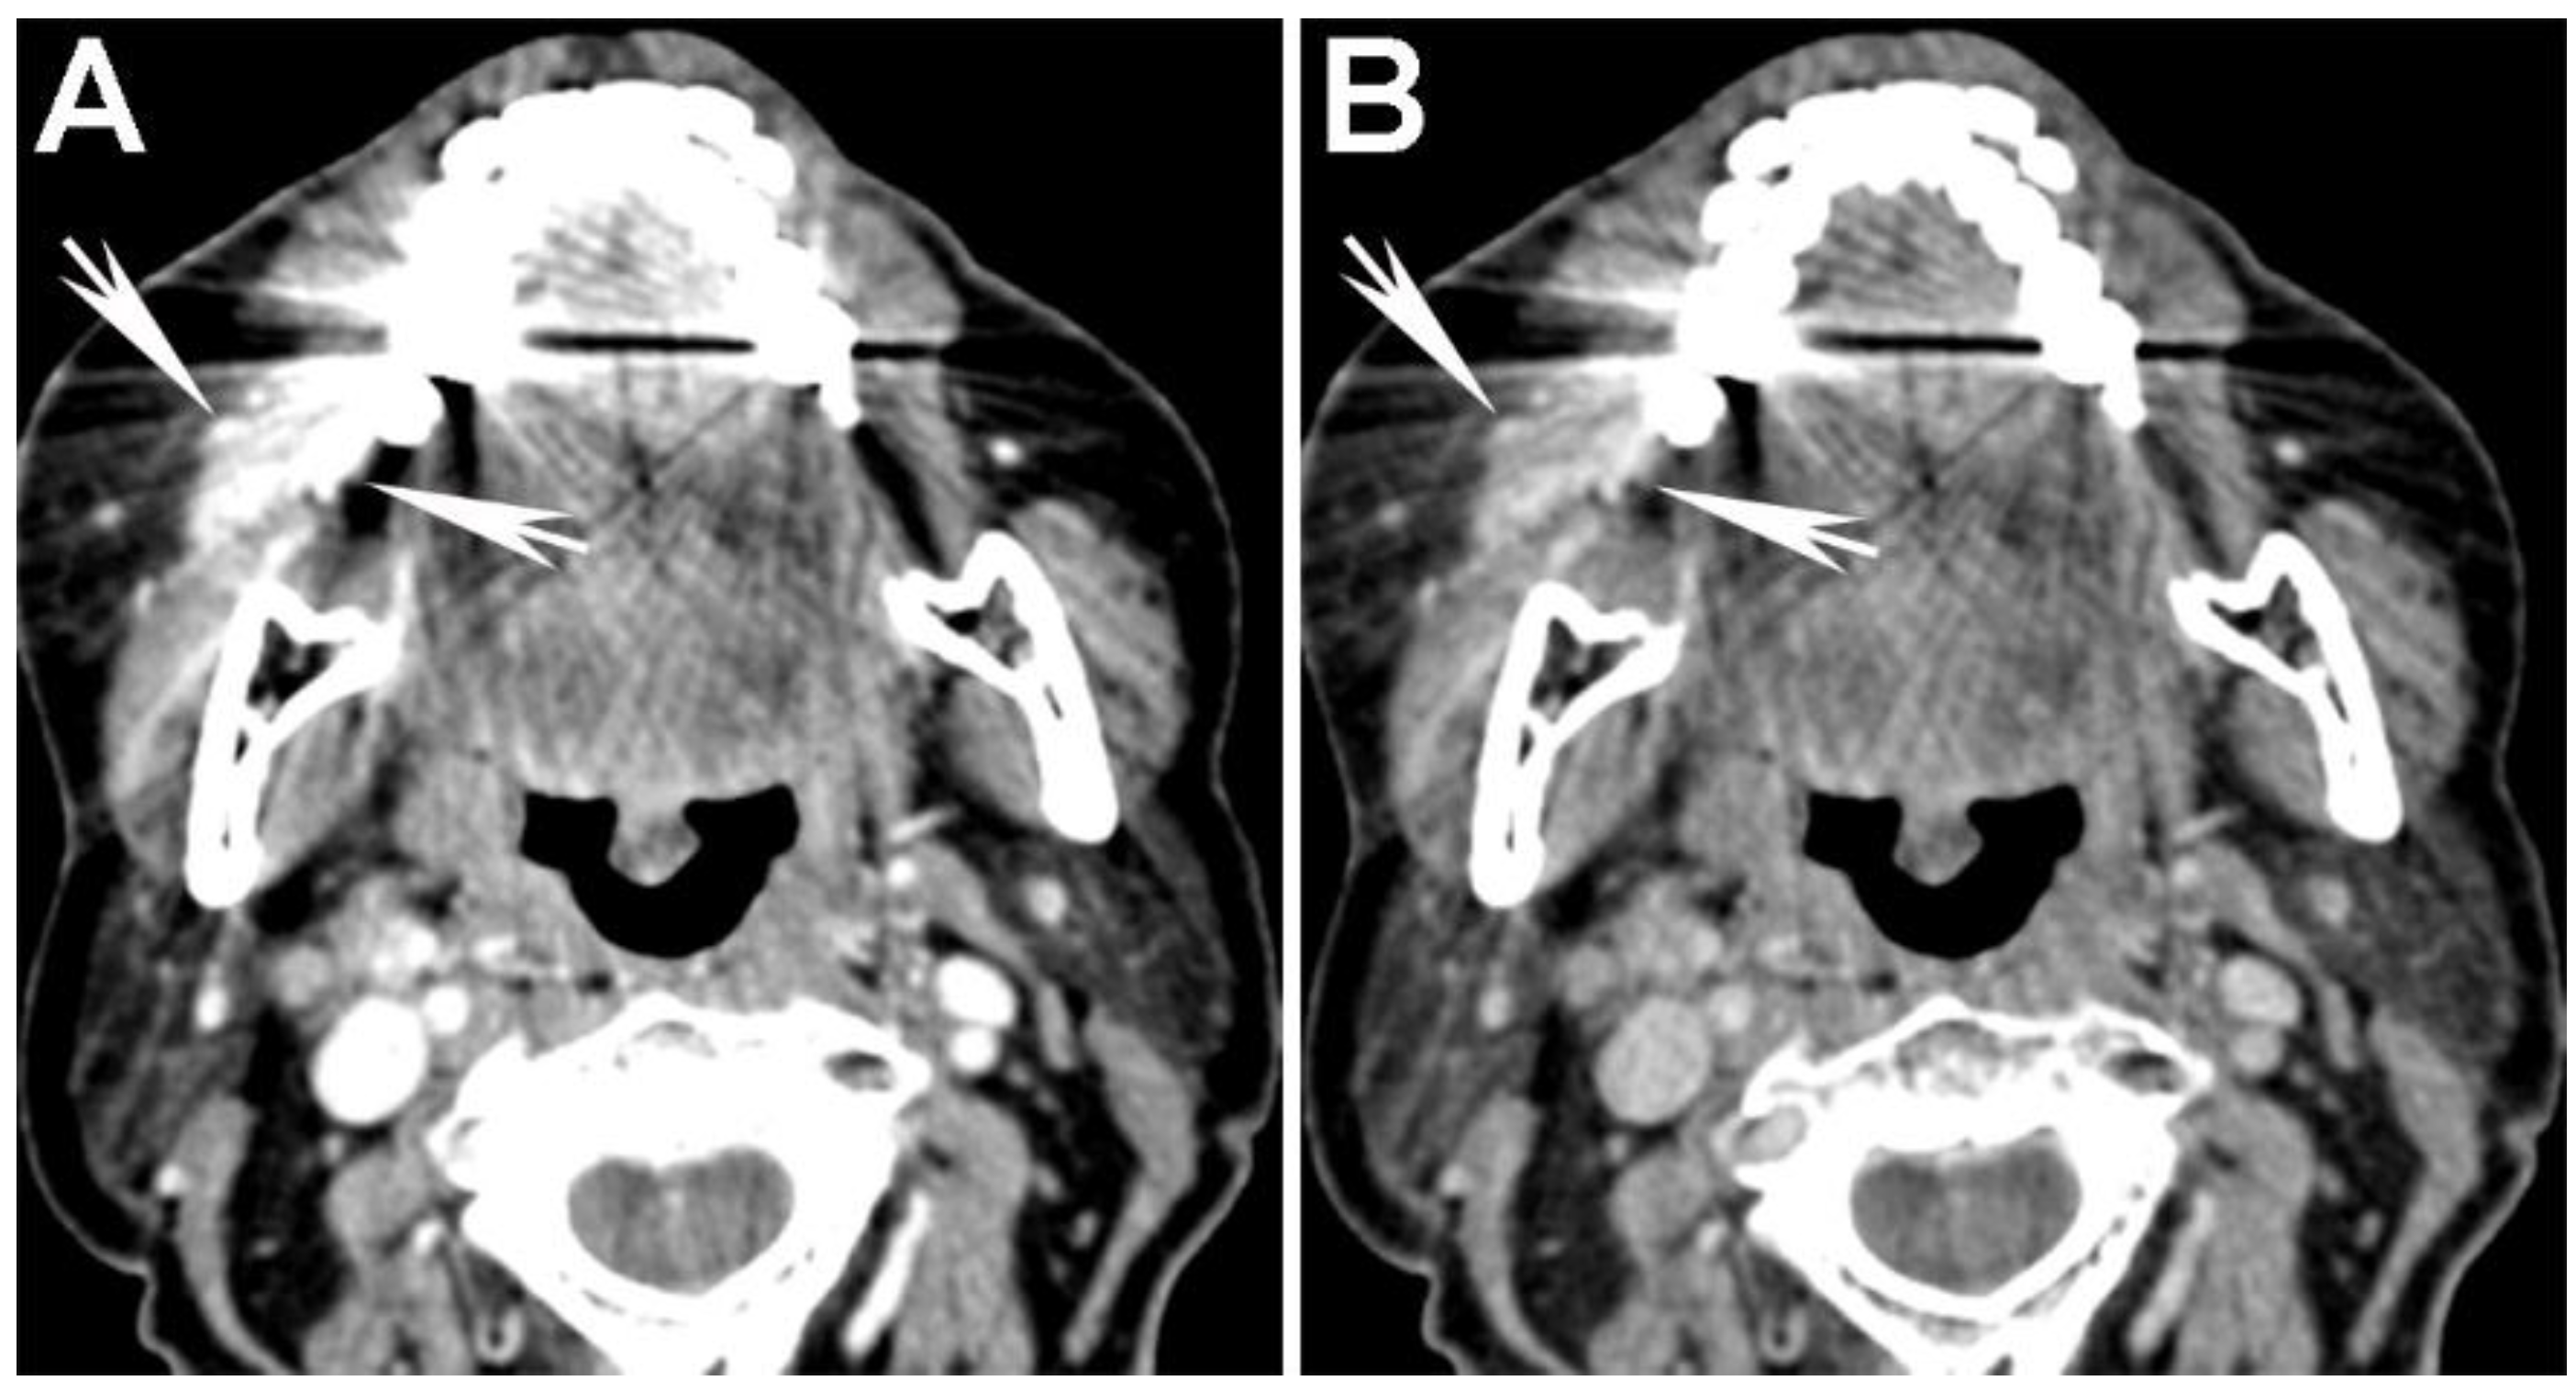

Figure 7. Use of high energy DECT virtual monochromatic images (VMIs) for dental artifact reduction in a patient with a gingival-buccal tumor. (A) 65 keV (equivalent to single energy CT) and (B) 95 keV VMIs are shown from the same level in the neck. Note reduction of artifact and improved visualization of the enhancing tumor on the 95 keV VMI compared to the 65 keV VMI.